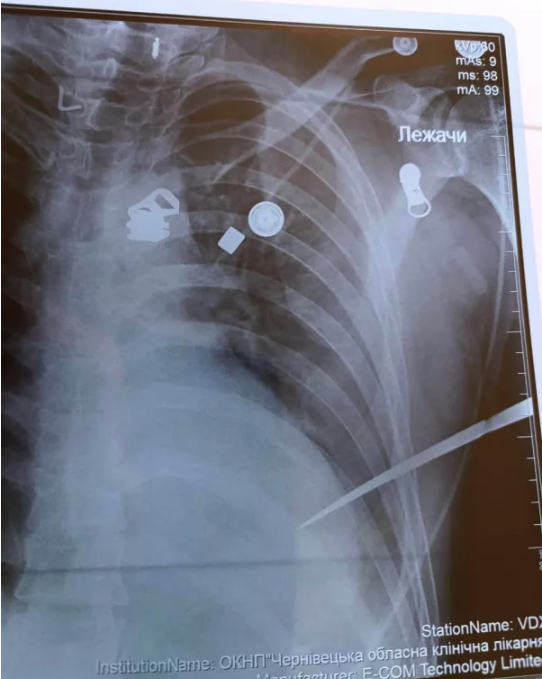

Рентген органів грудної клітки показав стороннє тіло в проєкції лівого шлуночка, кров у плевральній порожнині. УЗД серця, плевральних синусів, черевної порожнини – кров у перикарді (тампонада) та в плевральній порожнині. Потерпілого з приймального відділення доставили безпосередньо в операційну.